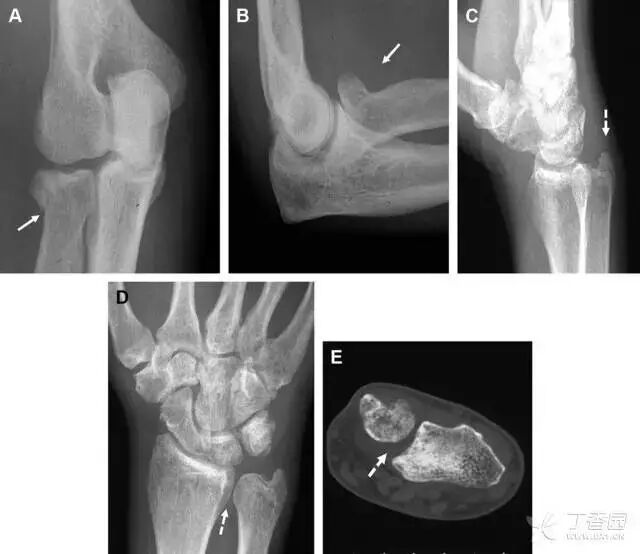

Essex-Lopresti 损伤

Essex-Lopresti 损伤是桡骨头骨折伴有下尺桡关节脱位,导致骨间膜损伤,桡骨短缩。此种损伤,桡骨头骨折的诊断往往是明确的,容易忽视的是下尺桡关节脱位,特别是早期,下尺桡关节的症状不明显,X 线表示也不明显。

图 8 Essex-Lopresti 损伤。前后位(A)和侧位(B)示桡骨头关节内骨折(白色实线箭头);(C~E)伤后 1 个月复诊,患者诉腕关节疼痛,X 线(C,D)发现下尺桡关节脱位,(E)CT 进一步证实损伤的存在

桡骨远端骨折

常规进行前后位、侧位、斜位 X 线检查,对于大多数桡骨远端骨折来说不容易漏诊;但是对于无移位的骨折,特别是桡骨茎突骨折,容易漏诊。桡骨茎突骨折是一斜行的骨折,常累及关节面,常发生于轴向应力或直接打击。

图 1 57 岁女性,摔倒后手掌撑地,桡骨茎突压痛。(A~C)前后位、斜位、侧位片示软组织肿胀(*)和发丝样骨折(白色箭头);(D~F)2 周后,前后位、斜位、侧位片示骨折线显明,由于新骨痂沉积而呈现透亮线与硬化线并存;(G~I)另一患者,桡骨茎突骨折在前后位及侧位片上显示不明显,而在斜位片显示更清楚。

舟状骨骨折

舟状骨骨折 60%~70% 发生于腰部,15% 发生于近极, 10% 发生于远极, 8% 发生于远端关节面。除了常规的前后位、侧位、斜位片外,还需要拍专门的舟状骨位片(腕关节尺偏,以舟状骨为中心的腕关节前后位片),特别是鼻烟壶有压痛时。

图 2 舟状骨骨折 (A、B)第 1 例患者,舟状骨远极关节内骨折(白色箭头),斜位片显示较清楚(B);(C、D)第 2 例患者,舟状骨腰部骨折(虚线箭头),斜位片显示较清楚(D);(E~H)第 3 例患者,舟状骨近极骨折,常规 X 线片均未看到骨折,而在舟状骨位片上才能见到骨折(虚线圆)。